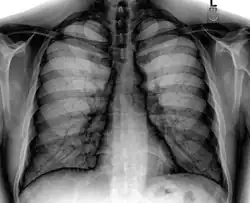

A chest radiograph with the angle parts of the ribs and some other landmarks labeled.